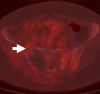

Purpose: To assess the feasibility of combined electromagnetic device tracking and computed tomography (CT)/ultrasonography (US)/fluorine 18 fluorodeoxyglucose (FDG) positron emission tomography (PET) fusion for real-time feedback during percutaneous and intraoperative biopsies and hepatic radiofrequency (RF) ablation.

Materials and methods: In this HIPAA-compliant, institutional review board-approved prospective study with written informed consent, 25 patients (17 men, eight women) underwent 33 percutaneous and three intraoperative biopsies of 36 FDG-avid targets between November 2007 and August 2010. One patient underwent biopsy and RF ablation of an FDG-avid hepatic focus. Targets demonstrated heterogeneous FDG uptake or were not well seen or were totally inapparent at conventional imaging. Preprocedural FDG PET scans were rigidly registered through a semiautomatic method to intraprocedural CT scans. Coaxial biopsy needle introducer tips and RF ablation electrode guider needle tips containing electromagnetic sensor coils were spatially tracked through an electromagnetic field generator. Real-time US scans were registered through a fiducial-based method, allowing US scans to be fused with intraprocedural CT and preacquired FDG PET scans. A visual display of US/CT image fusion with overlaid coregistered FDG PET targets was used for guidance; navigation software enabled real-time biopsy needle and needle electrode navigation and feedback.

Results: Successful fusion of real-time US to coregistered CT and FDG PET scans was achieved in all patients. Thirty-one of 36 biopsies were diagnostic (malignancy in 18 cases, benign processes in 13 cases). RF ablation resulted in resolution of targeted FDG avidity, with no local treatment failure during short follow-up (56 days).

Conclusion: Combined electromagnetic device tracking and image fusion with real-time feedback may facilitate biopsies and ablations of focal FDG PET abnormalities that would be challenging with conventional image guidance.